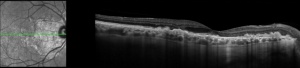

Spectral domain optical coherence tomography (SD-OCT) imaging can reveal focal dome-shaped, saw-tooth, or diffuse hyperreflective deposits with elevation between the RPE and Bruch's membrane, usually becoming more confluent over time[11]. Early in disease, the outer retina (photoreceptors) may remain intact, but later stages can show variable or diffuse ellipsoid zone loss, as well as outer and inner segment disruption. OCT can also reveal hypo-reflective fluid from a corresponding neovascular membrane. Diffuse retinal atrophy can be seen in later stages, however outer retinal changes are not often seen outside of areas with sub-RPE changes[12].

OCT-A is also a useful imaging modality that can be used in visualization of DHRD. Choriocapillaris segmentation of OCT-A in DHRD patients has shown a hyperflow signal corresponding to active choroidal neovascularization. [15]